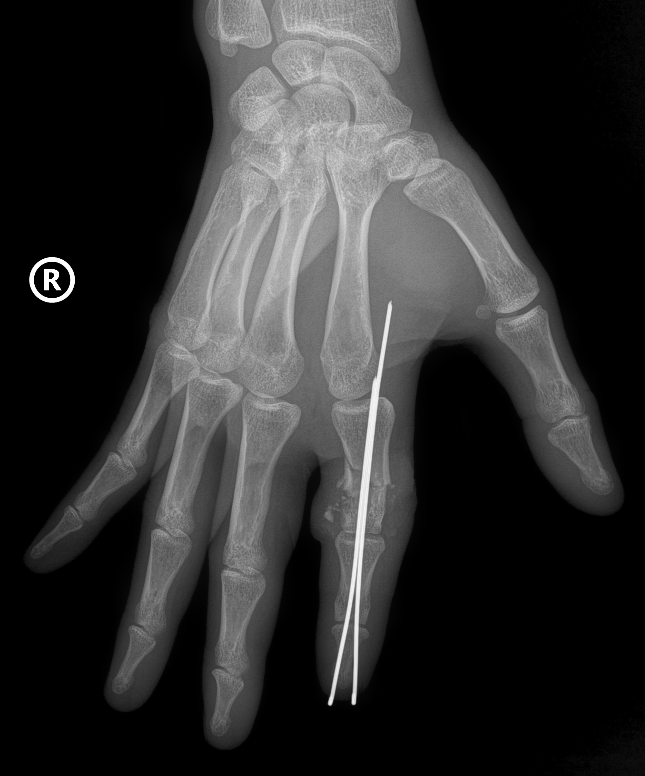

Tại phòng mổ, kíp phẫu thuật cấp cứu được triển khai với sự phối hợp đa chuyên khoa: vi phẫu tạo hình, gây mê hồi sức, chấn thương chỉnh hình… Hai kíp phẫu thuật được triển khai song song, một kíp làm sạch và chuẩn bị phần ngón đứt rời, kíp còn lại chuẩn bị phần mỏm cụt. Xương ngón được định vị và cố định bằng kim chuyên dụng để tạo trục vững, hệ thống gân và dây chằng được phục hồi. Đặc biệt là thần kinh và các mạch máu nhỏ li ti chỉ khoảng 0,8 - 1mm được phục hồi với độ chính xác cao dưới kính hiển vi phẫu thuật với dụng cụ đặc biệt nhằm đảm bảo phục hồi lưu thông tưới máu cho phần đứt rời.

Sau phẫu thuật, vết thương đã liền, ngón tay hồng, sống hoàn toàn, người bệnh đã có thể cắt chỉ và rút kim cố định. Người bệnh đang được tập phục hồi chức năng để lấy lại khả năng vận động và cảm giác của ngón tay.